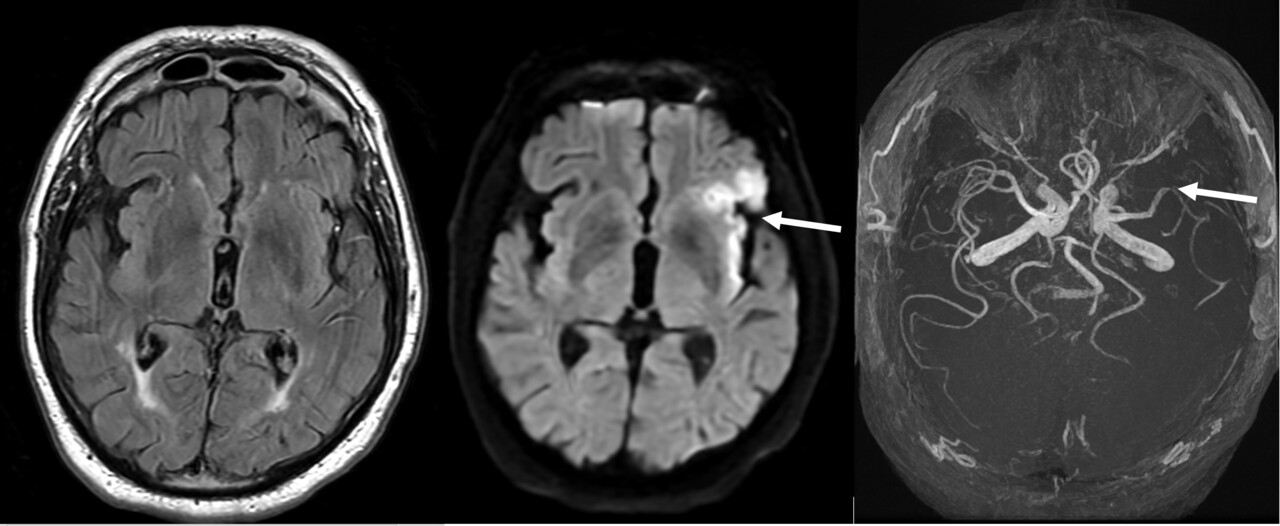

Mme X, 55 ans, sans antécédents médicaux notables, consulte pour un épisode de paresthésie transitoire du membre supérieur droit et une aphasie. L’examen clinique révèle un livedo racemosa marqué au niveau des membres inférieurs et du tronc (fig. 1). L’IRM cérébrale met en évidence des lésions ischémiques multiples en territoire sylvien superficiel gauche (fig. 2). Le bilan immunologique retrouve la présence d’anticorps antiphospholipides (anticardiolipines et anticoagulants lupiques).